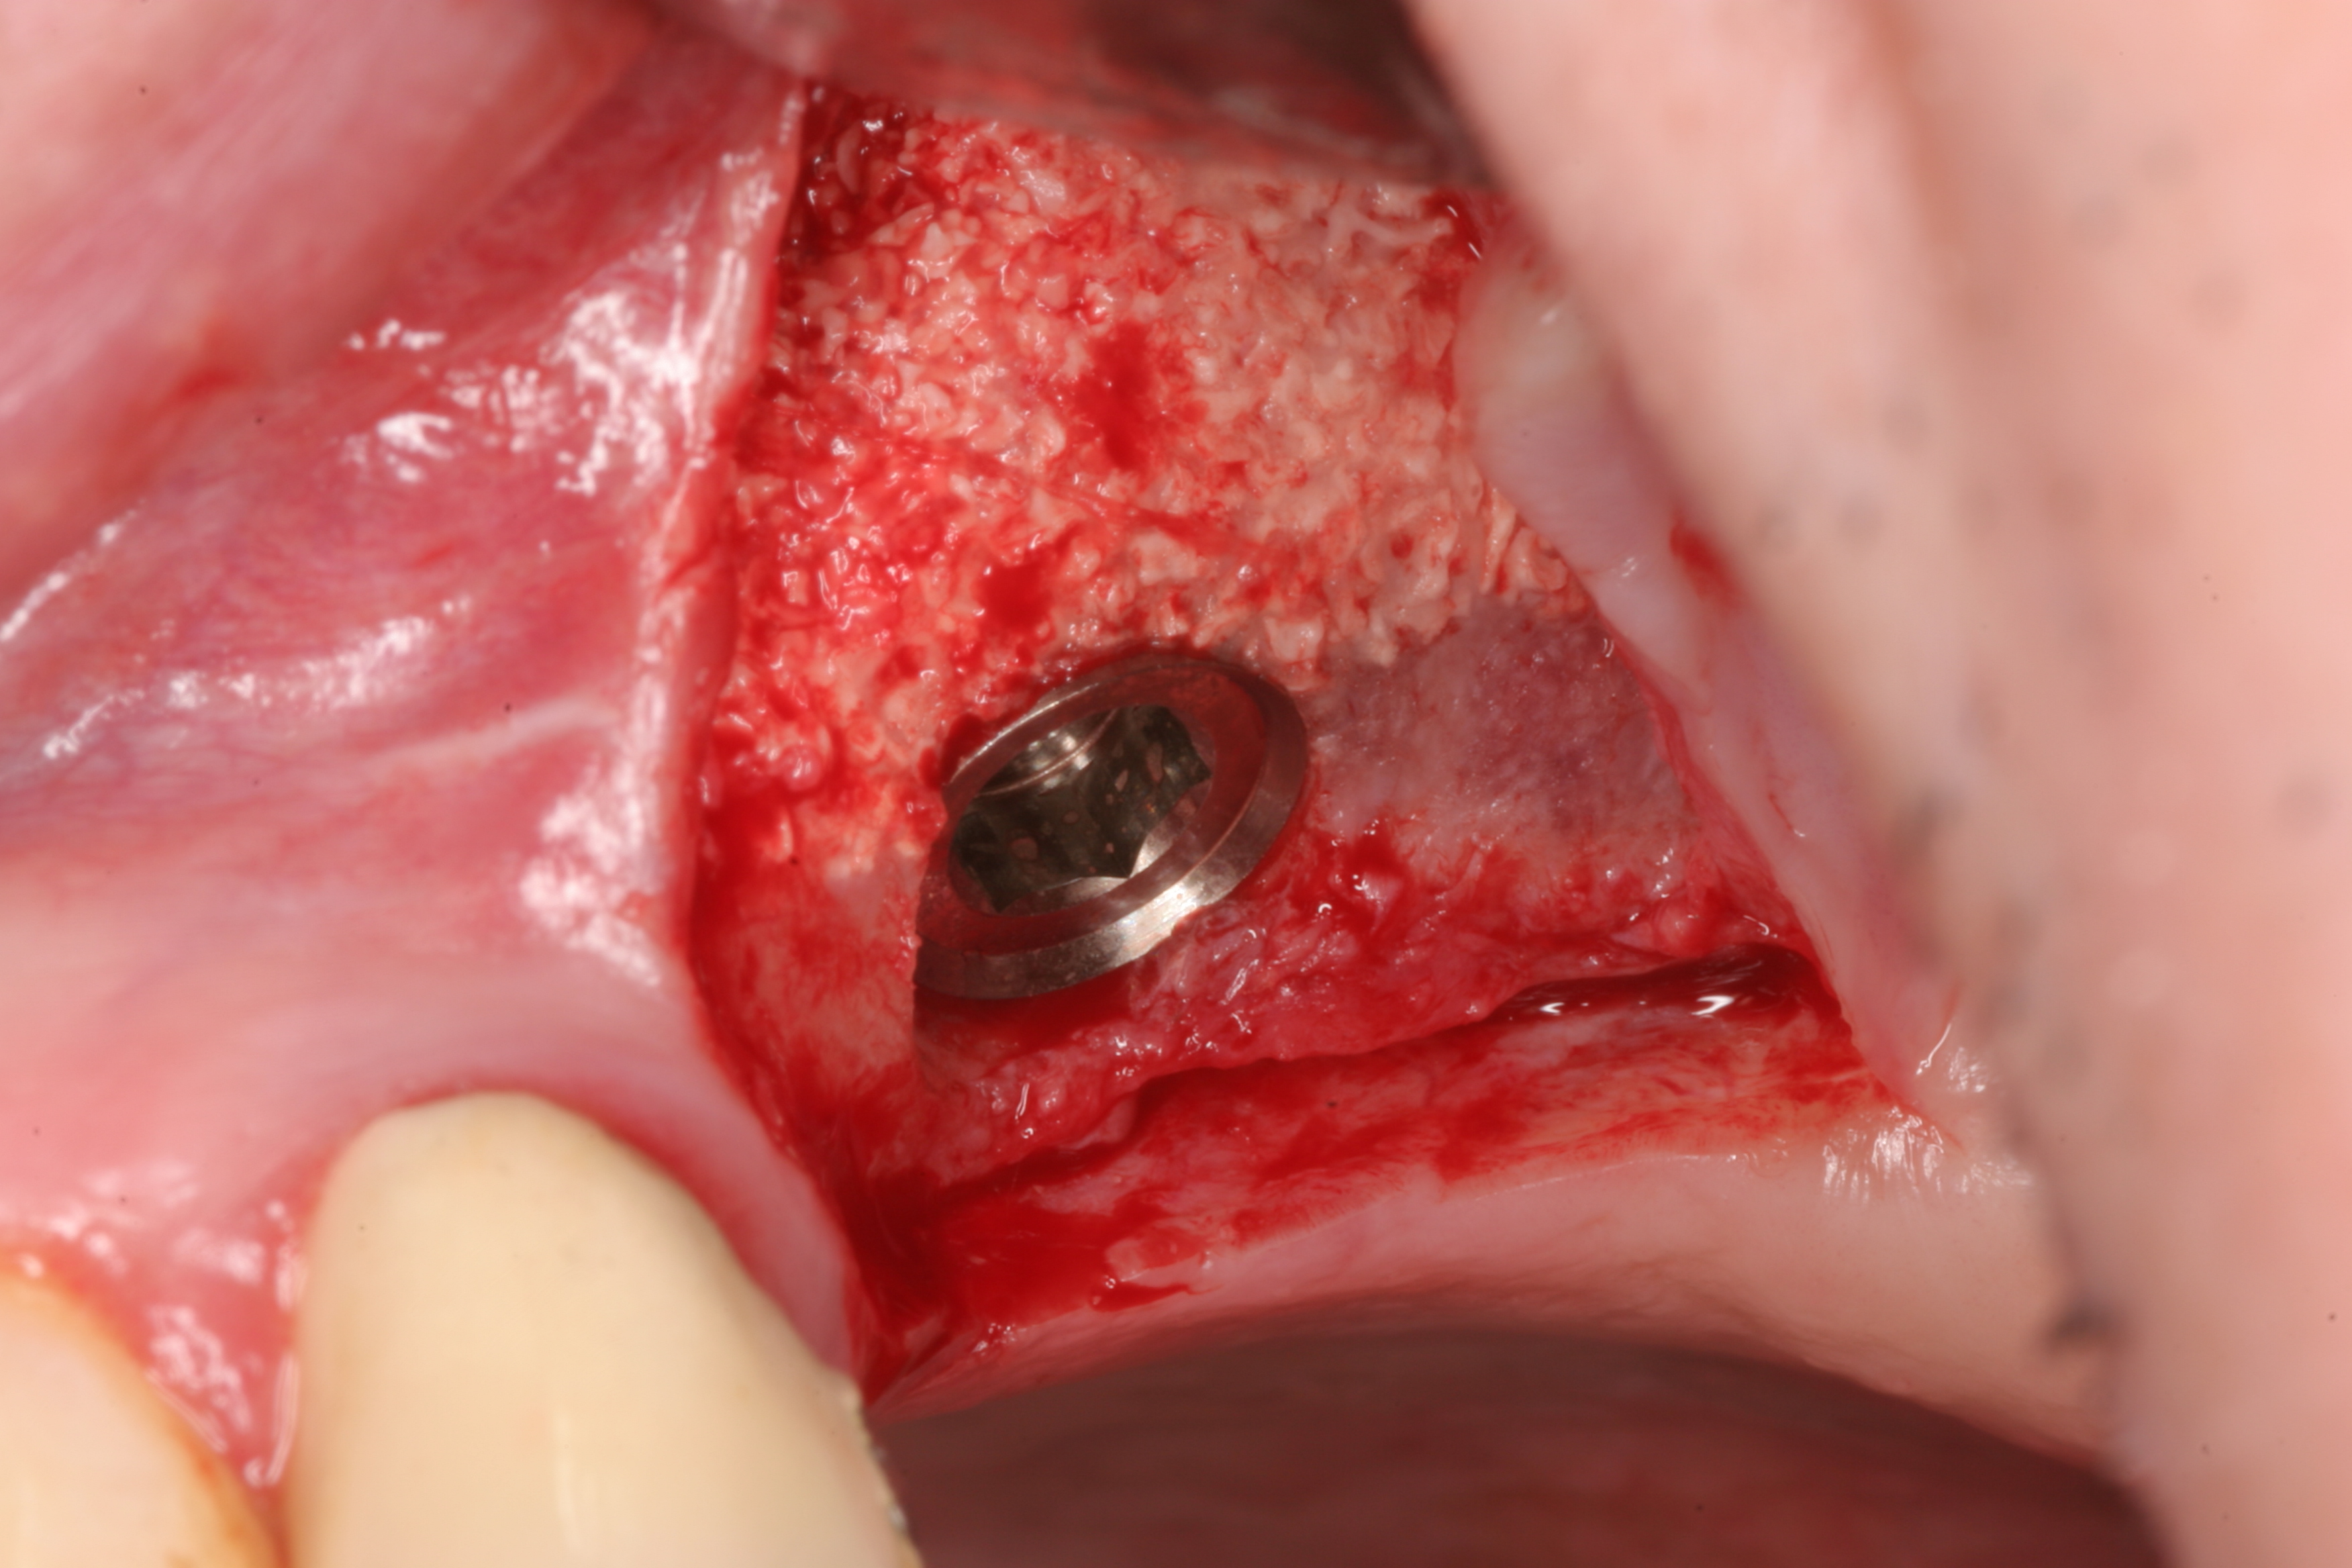

16/19 - Implant insertion with the help of a drilling templateSinus lift two-stage with cerabone® and Jason® membrane - Prof. Dr. Dr. D. Rothamel

17/19 - Implant placed in sufficient bone matrixSinus lift two-stage with cerabone® and Jason® membrane - Prof. Dr. Dr. D. Rothamel